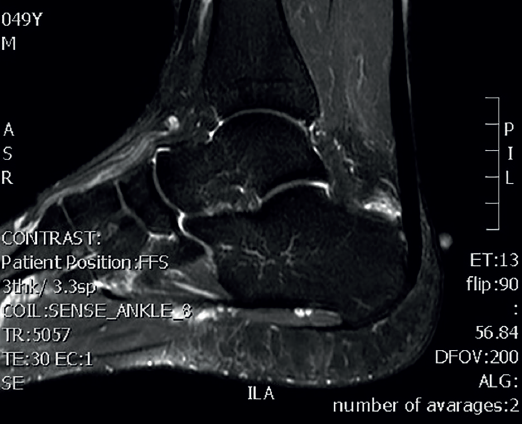

Ultrasound allows us to identify inflammatory signs in both bursae, tendon lesions and bone exostosis. Tendon degeneration is characterised by poorer echogenicity (a lower mean value on the scale of greys), due to the lesser organisation and altered composition of the tendon microstructure(21). Doppler ultrasound in turn allows us to assess neovascularisation zones (Figure 4). Ultrasound offers dynamic exploration and is operator-dependent.

Figure 4. Ultrasound exploration. Retrocalcaneal bursitis and signs of tendinopathy (yellow arrows). Doppler ultrasound allows the identification of tendon hypervascularisation areas.